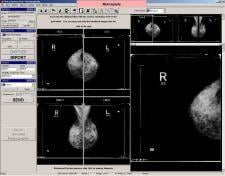

The CAD PRO Advantage digitizer specifically designed for mammography, reportedly provides the ability to quickly digitize film-based prior studies and, when coupled with the appropriate software, uses the DICOM MG standard to identify the specific mammography view contained on each film.

The CAD PRO Advantage offers a modular 50-sheet film feeder. The design of VIDAR's SmartFeeder reportedly eliminates film jams, double feeds and film pick-up problems that may occur. The CAD PRO Advantage feeder is designed for continuous case loading, allowing the user to add cases without interrupting the digitizing process. In addition, the CAD PRO Advantage is reportedly able to digitize a four-film case in less than 120 seconds.